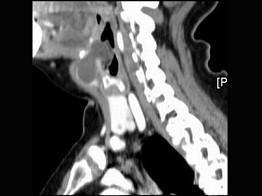

3.女,57岁,颈部不适,CT如图所示,应诊断为 ( )![]() ![]() ![]() ![]() |

| 正确答案:C |